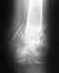

Re: Многооскольчатый перелом локтевого отростка

Компьютерная томограмма от 23.06.2009.